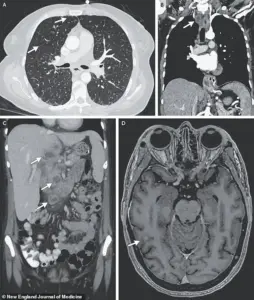

X-ray scans revealed an alarming finding: multiple small nodules scattered across her lungs, a hallmark sign of bacterial infection.

Further imaging and biopsies painted a more sinister picture.

Lesions were detected in her liver, lymph nodes, pancreas, and brain—organs that should have been untouched by the disease.

A recent case study highlights this grim reality: a woman’s scans revealed nodules in her lungs, liver, pancreas, and brain, with an enlarged lymph node in her chest.

These findings, though rare, underscore the disease’s potential to evade detection and wreak havoc on multiple organ systems.